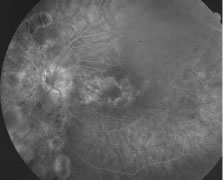

Both herpes simplex virus type 1 and herpes simplex virus type 2 (HSV-1, HSV-2) may cause ARN.20–22 In a single report, CMV particles were identified in and cultured from the retina of an enucleated eye of a nonimmunosuppressed patient suffering from bilateral ARN.23 VZV has been reported most frequently as the viral etiologic agent of ARN.2,3,24–27 We have demonstrated herpesvirus family viral particles in endoretinal biopsy specimens taken from patients in the active stage of the disease who showed an enormous viral load (Fig. 4). These studies, combined with the failure of many enucleated eyes with ARN to demonstrate evidence of viral particles, indicate that the virus is present only in the active stages of the disease and that a gliotic retina will not demonstrate the etiologic agent.28